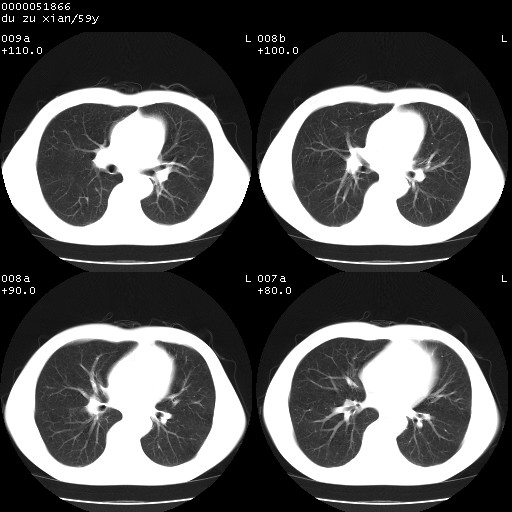

以下是引用宇宙ct在2008-8-25 23:21:00的发言:[br]右肺周围性肺癌并肋骨转移,纵隔淋巴结转移。

以下是引用zsl6918在2008-8-25 22:40:00的发言:[br]右肺周围性肺癌并肋骨转移,纵隔淋巴结转移。

以下是引用zy_zj在2008-8-26 15:24:00的发言:[br]单从病变本身,我倾向良性炎性病变,但肋骨转移了,所以说是考虑右肺周围性肺癌并肋骨、纵隔淋巴结转移可能性大。